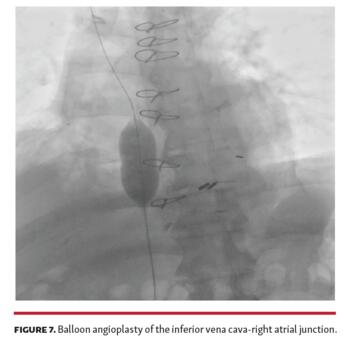

IVC stenosis is a rare complication of bicaval orthotopic heart transplant. IVC stenosis can occur at either the cavoatrial anastomosis or the caval cannulation site, with presentations ranging from acute shock early post transplant to a more indolent course. Causes include extensive hemostatic suturing, fibrous contraction, and donor-recipient size mismatch. Treatment strategies include percutaneous balloon angioplasty (Figure 7), stenting (Figure 8), and surgical revision. Evaluating for IVC stenosis is recommended for unexplained lower extremity edema, new-onset ascites, or liver abnormalities after bicaval heart transplant.